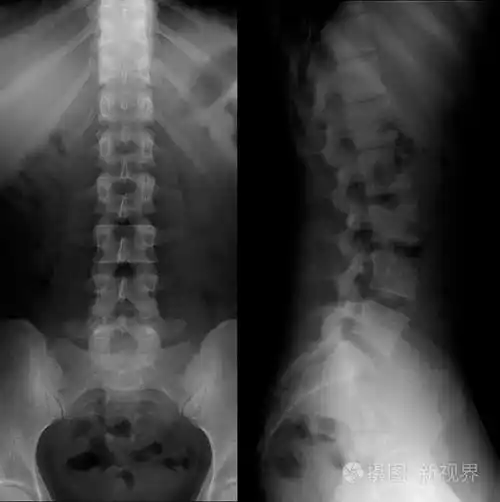

腰骶椎x线正常的完美

腰椎x光片

腰椎x光

正常腰椎

脊柱x射线

典型案例二:男,48岁,腰椎间盘突出.